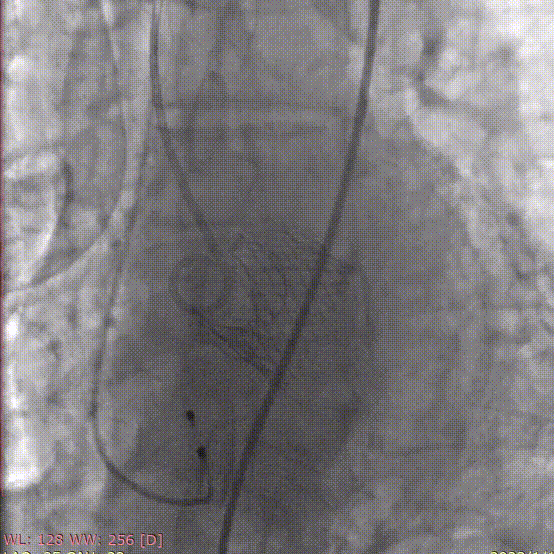

术前造影

定位件入窦

释放瓣膜

术后造影

术中采用局麻强化,经股动脉穿刺建立血管通路,首先采用25mm球囊对病变部位进行预扩张,预扩时无明显腰征及反流,之后将杰成主动脉瓣输送器送入主动脉瓣目标位置,轻松实现定位件的正确入窦,后成功释放25mm瓣膜,之后采用25mm球囊进行后扩张。

经DSA造影和超声等综合评估显示瓣膜释放位置完美,瓣膜工作稳定,术后即刻主动脉瓣上峰值流速:202cm/s、峰值压力阶差:15mmHg,平均压差:7mmHg,人工主动脉瓣瓣环内无反流,微量瓣周漏,患者临床症状和血流动力学明显改善。